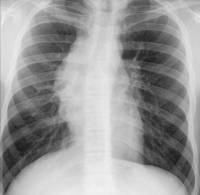

CT

Abbildung 2: Zugehöriges CT-Bild; ein ausgedehntes Thymom mit Kompression und Infiltration der V. cava superior (Pfeil).